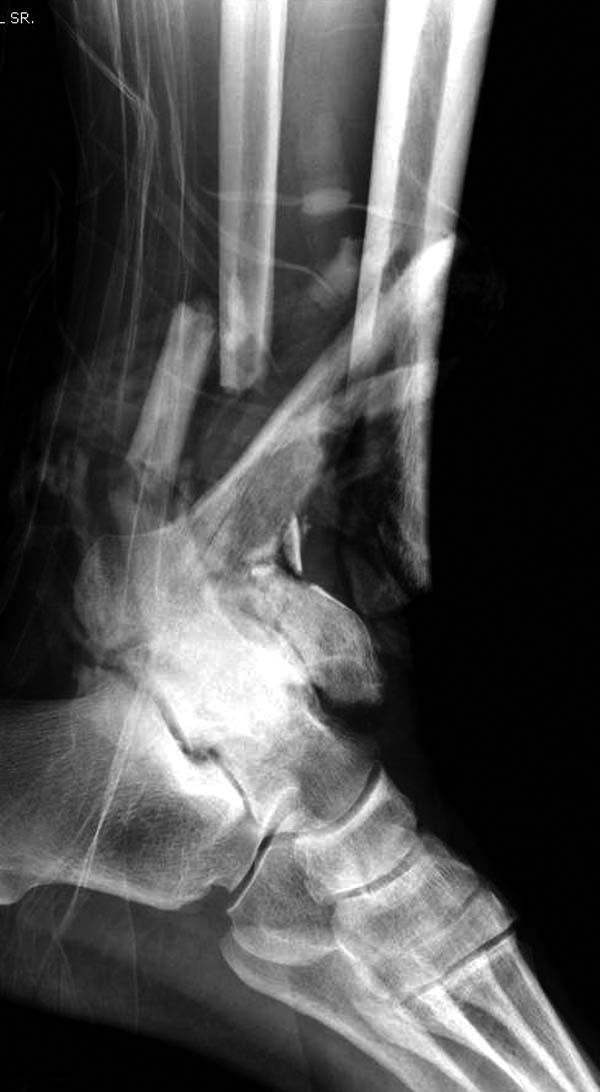

В нашем случае, травма в результате коллапса крыши. Открытый перелом. Ургентные Irrigation and Debridment, дистракция наружным фиксатором. В госпиталях первого уровня редко бывает изолированная травма, и на другой стороне повреждение стопы с переломом навикулярной кости. После обработки раны - вакуум и двухсторонние наружные фиксаторы.

Вначале нет смысла заказывает КТ, только дистракция организует на свое место свободных фрагментов. По топографии отломком преоперационный план, а готовность мягкой ткани подтвердит появившиеся морщины на поверхности кожи, “Wrinkle Sign”.